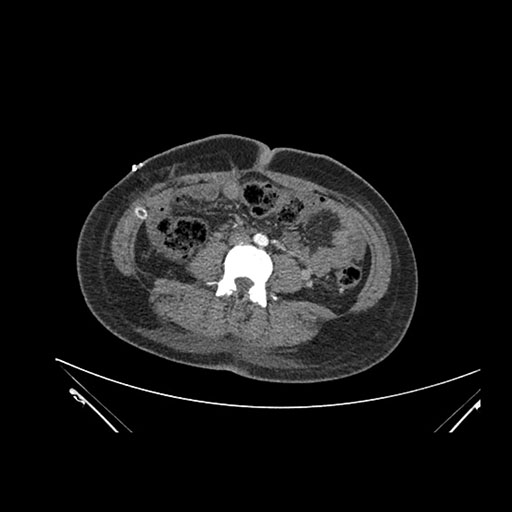

Imaging Analysis

Look through the patient's CT scan to identify any areas of concern for the necessary procedure.

Coronal Venous

Based on initial findings, which issue(s) would you be most concerned about?